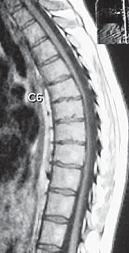

МРТ № 52

На МРТ № 52 наблюдается усиление грудного кифоза (гиперкифоз), снижение высоты межпозвонковых дисков с деформацией замыкательных пластин, расширением тел позвонков в вершине кифоза и самое главное — перерастяжение и уплощение спинного мозга на уровне вершины искривления.

Рассмотрим вариант нормы и патологии грудного отдела позвоночника (МРТ № 51, МРТ № 52). Конечно, заболеваний, которые могут проявиться вследствие развития остеохондроза грудного отдела позвоночника, достаточно. В каждом отдельном случае необходимо установить точный диагноз, осуществить грамотный подход в выборе методов лечения. Нельзя недооценивать возможные вариации развития заболевания. Вот, например, из-за таких деформаций позвоночника, которые можно наблюдать на МРТ № 52, порой возникают парезы или параличи, зачастую вследствие развивающегося ишемического «миелита», точнее спондилогенной миелопатии — перерождение вещества спинного мозга из-за недостаточного кровоснабжения. Причём то же клиническое течение спондилогенной миелопатии может протекать двояко. Чаще заболевание развивается исподволь, постепенно в течение довольно длительного времени. Порой останавливается, так и не достигнув своего апогея. А бывает (хотя и намного реже) в течение относительно короткого отрезка времени, на фоне полноценной функции спинного мозга, возникают парезы и параличи. Что лежит в основе этого тяжелейшего осложнения — спондилогенной миелопатии? Как правило, расстройство кровоснабжения спинного мозга. Оно, в свою очередь, возникает вследствие нарушения проходимости питающих его артериальных кровеносных сосудов. Опасность здесь таится в том, что значительный по длине спинной мозг, занимающий почти всю протяжённость позвоночника, получает кровоснабжение всего из нескольких артерий. Если даже одна из таких питающих артерий вследствие перерастяжения или сдавления «закупоривается», то значительные территории спинного мозга лишаются кислорода, питательных и других веществ, что приносит с собой его тканям артериальная кровь. Нарушение проходимости питающих спинной мозг кровеносных сосудов возникает вследствие их перерастяжения вместе со спинным мозгом и его элементами, что или приводит к сужению просвета растянутого артериального ствола или к прямому сдавлению его деформированными костными структурами позвоночника. Нервная ткань спинного мозга очень чуткая к недостаточности кровоснабжения и быстро гибнет в условиях неполноценного притока артериальной крови. Это, в свою очередь, приводит к возникновению частичных и полных параличей тех органов, которые зависят от поражённых территорий спинного мозга. Вот такая выстраивается цепочка, где одно событие неумолимо порождает другое и приводит к определённым последствиям.